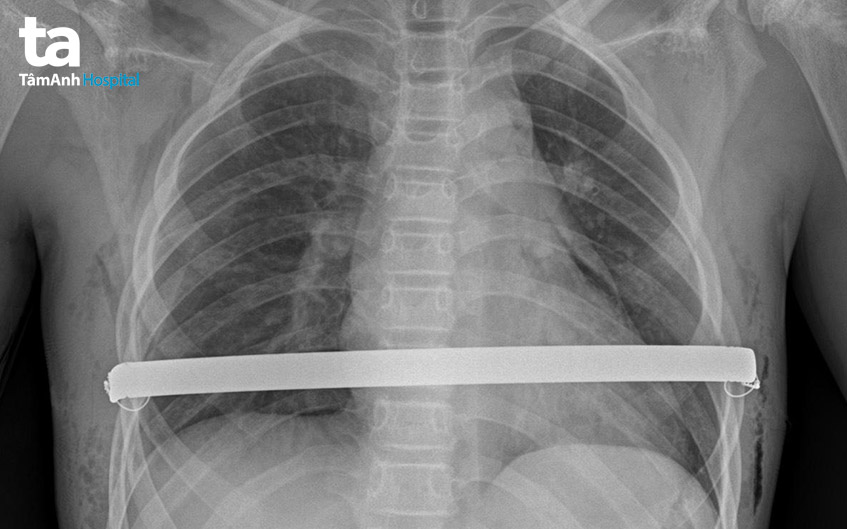

Bước vào ca phẫu thuật lõm xương ức, các bác sĩ mở hai đường nhỏ phía trước bên thành ngực để tạo ra một đường hầm đưa thanh kim loại vào. Sau đó, thanh kim loại cong được xoay 180 độ lên trên, đẩy xương ức phồng lên và được cố định vào khung sườn. Một camera được đặt vào lồng ngực trong suốt quá trình phẫu thuật, giúp bác sĩ quan sát rõ tim và các mạch máu lớn để không làm tổn thương những cơ quan này. Sau phẫu thuật, dị dạng vùng ngực của Mạnh được khắc phục hoàn toàn. Sức khỏe bệnh nhi ổn định và xuất viện sau 5 ngày.

Sau ca phẫu thuật lõm ngực, trẻ được tái khám theo lịch. Khoảng 2 năm kể từ ngày phẫu thuật, xương ức ổn định, cứng chắc ở tư thế phẳng, bệnh nhân sẽ được thực hiện phẫu thuật lần hai để rút thanh nâng ngực, kết thúc quá trình điều trị. Theo bác sĩ Dũng, trường hợp trẻ phẫu thuật sau 18 tuổi thường phải để lâu hơn, từ 3-4 năm mới rút thanh nâng ngực.